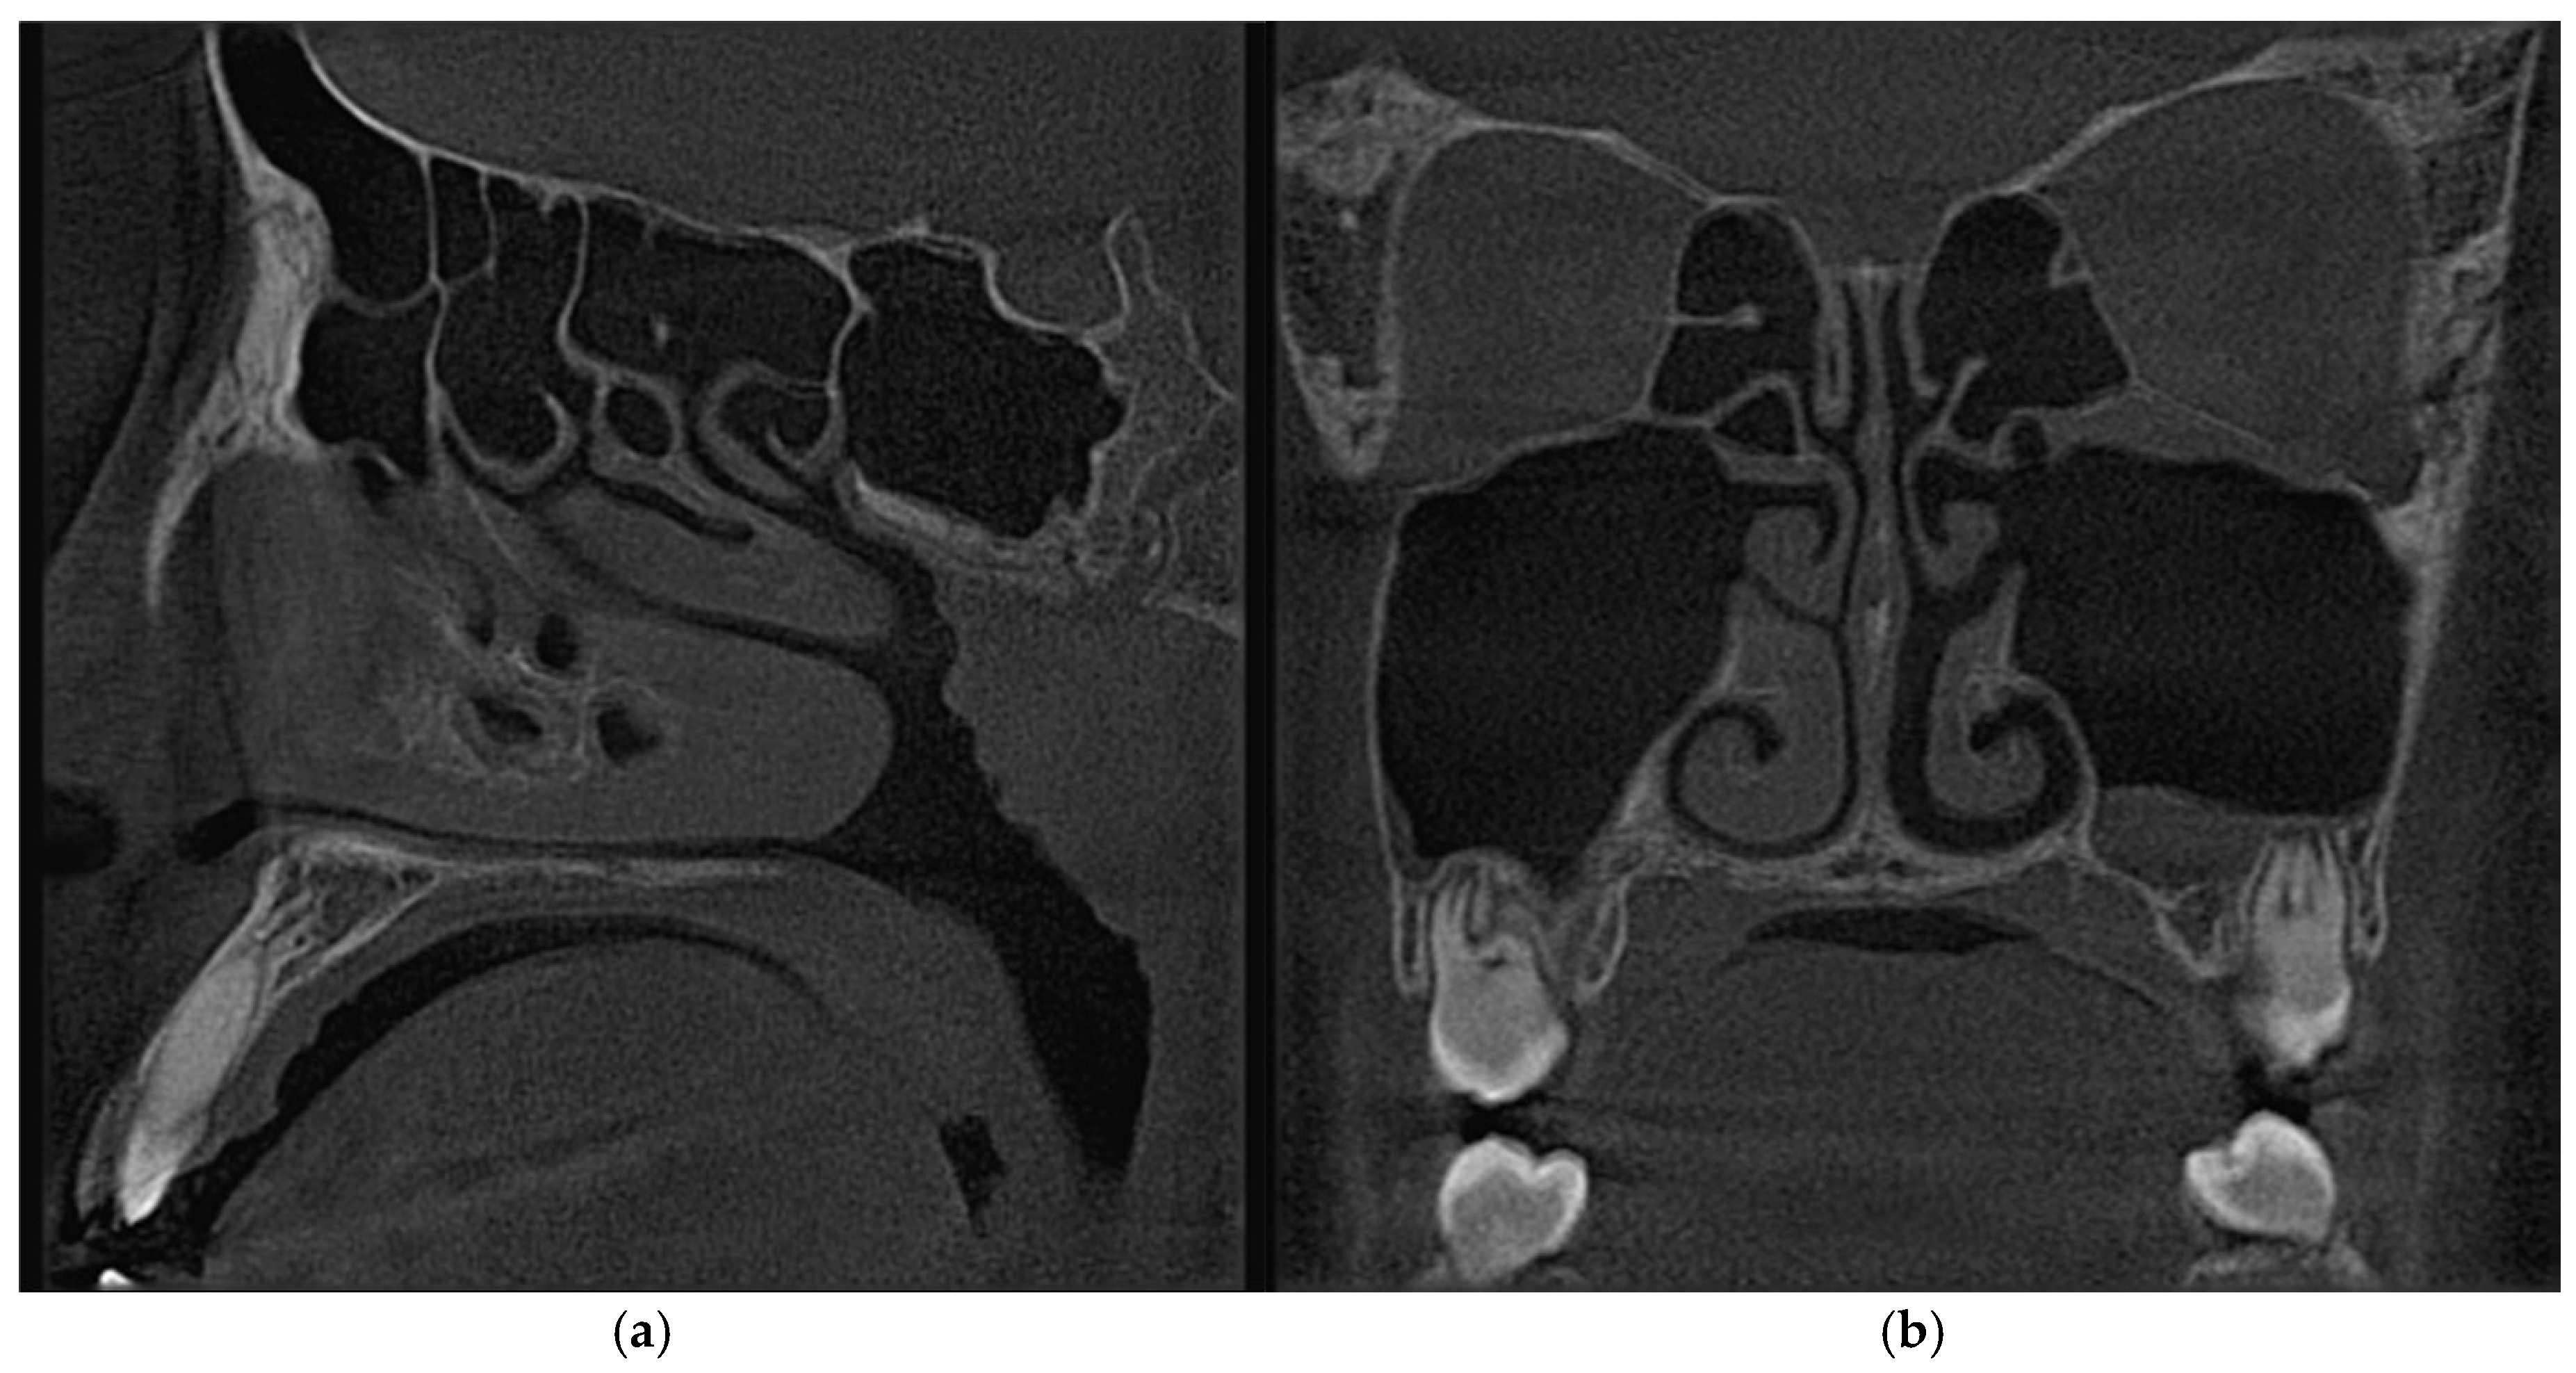

3.3. Patient Case Report